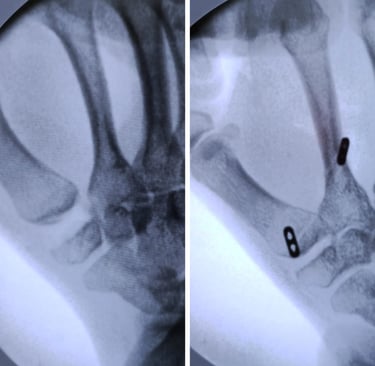

Estabilidad definitiva para casos avanzados

La artrodesis trapeciometacarpiana por artroscopia permite tratar la rizartrosis avanzada mediante la fusión controlada de la articulación, preservando la biomecánica del pulgar y reduciendo el dolor de forma definitiva. La asistencia artroscópica facilita una preparación precisa de las superficies articulares y una mínima agresión tisular, mientras que los tornillos canulados cruzados aportan una fijación sólida y fiable.